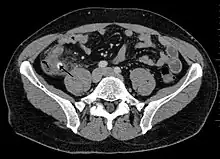

Appendicitis as seen on CT imaging

A CT scan demonstrating acute appendicitis (note the appendix has a diameter of 17.1 mm and there is surrounding fat stranding)

A fecalith marked by the arrow that has resulted in acute appendicitis.

Where it is readily available, computed tomography (CT) has become frequently used, especially in people whose diagnosis is not obvious on history and physical examination. Although some concerns about interpretation are identified, a 2019 Cochrane review found that sensitivity and specificity of CT for the diagnosis of acute appendicitis in adults was high.[59] Concerns about radiation tend to limit use of CT in pregnant women and children, especially with the increasingly widespread usage of MRI.[60][61]

The accurate diagnosis of appendicitis is multi-tiered, with the size of the appendix having the strongest positive predictive value, while indirect features can either increase or decrease sensitivity and specificity. A size of over 6 mm is both 95% sensitive and specific for appendicitis.[62]

However, because the appendix can be filled with fecal material, causing intraluminal distention, this criterion has shown limited utility in more recent meta-analyses.[63] This is as opposed to ultrasound, in which the wall of the appendix can be more easily distinguished from intraluminal feces. In such scenarios, ancillary features such as increased wall enhancement as compared to adjacent bowel and inflammation of the surrounding fat, or fat stranding, can be supportive of the diagnosis. However, their absence does not preclude it. In severe cases with perforation, an adjacent phlegmon or abscess can be seen. Dense fluid layering in the pelvis can also result, related to either pus or enteric spillage. When patients are thin or younger, the relative absence of fat can make the appendix and surrounding fat stranding difficult to see.[63]